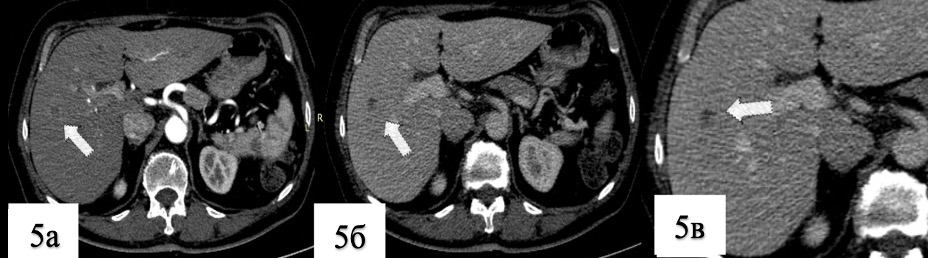

5. Риc. 5. КТ сканы живота

Тема

Тип Исследовательские инструменты